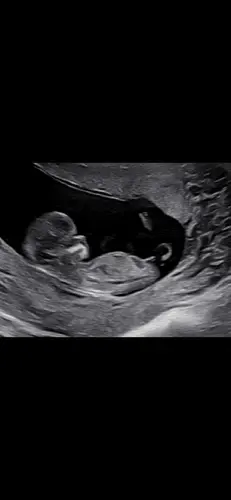

Dit was met 11 weken!

Jongetje… hoewel nog vroeg, zie je wel al een stijgende nub.